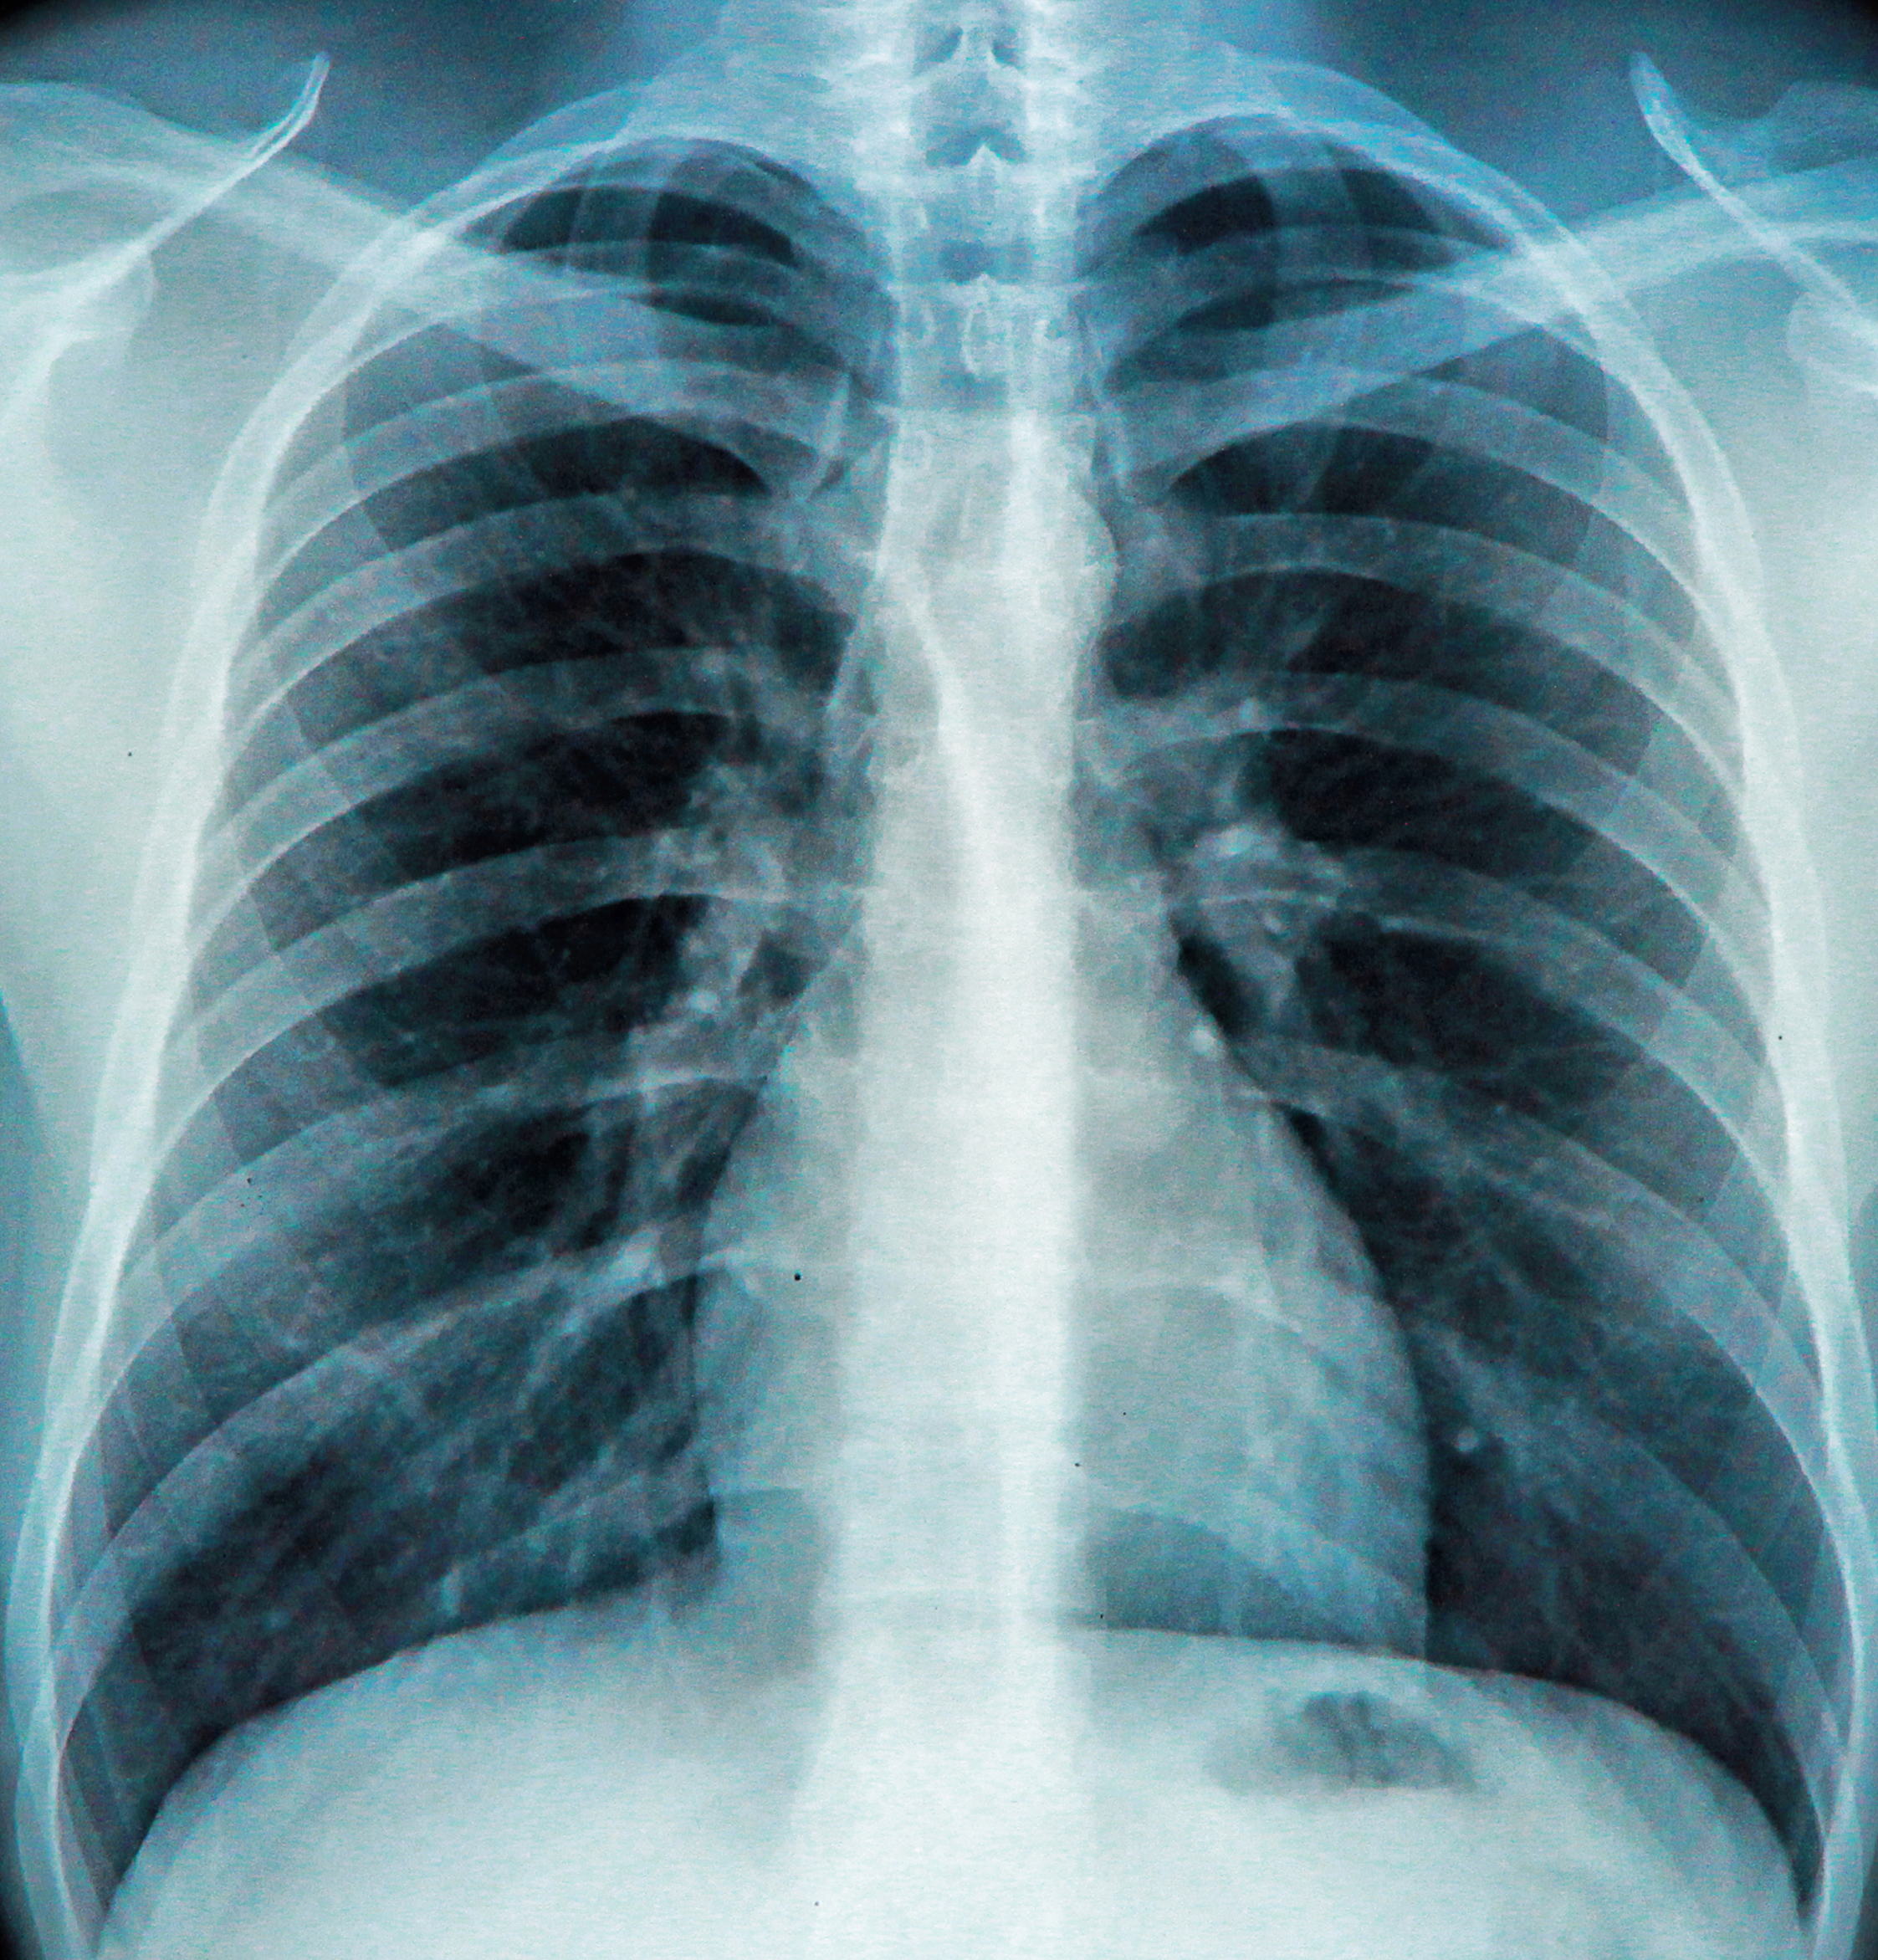

Radiografia torace

Che cos'è la radiografia emitorace?

La radiografia dell'emitorace è un esame diagnostico che utilizza i raggi X per creare immagini dettagliate delle strutture presenti in una metà del torace.

Questo esame permette di visualizzare le ossa, come le costole e la colonna vertebrale, e i tessuti molli, inclusi i polmoni e il cuore.

L'esame viene condotto utilizzando un fascio di raggi X che attraversa il corpo e si imprime su una pellicola o un sensore digitale, creando un'immagine fotografica delle strutture interne.